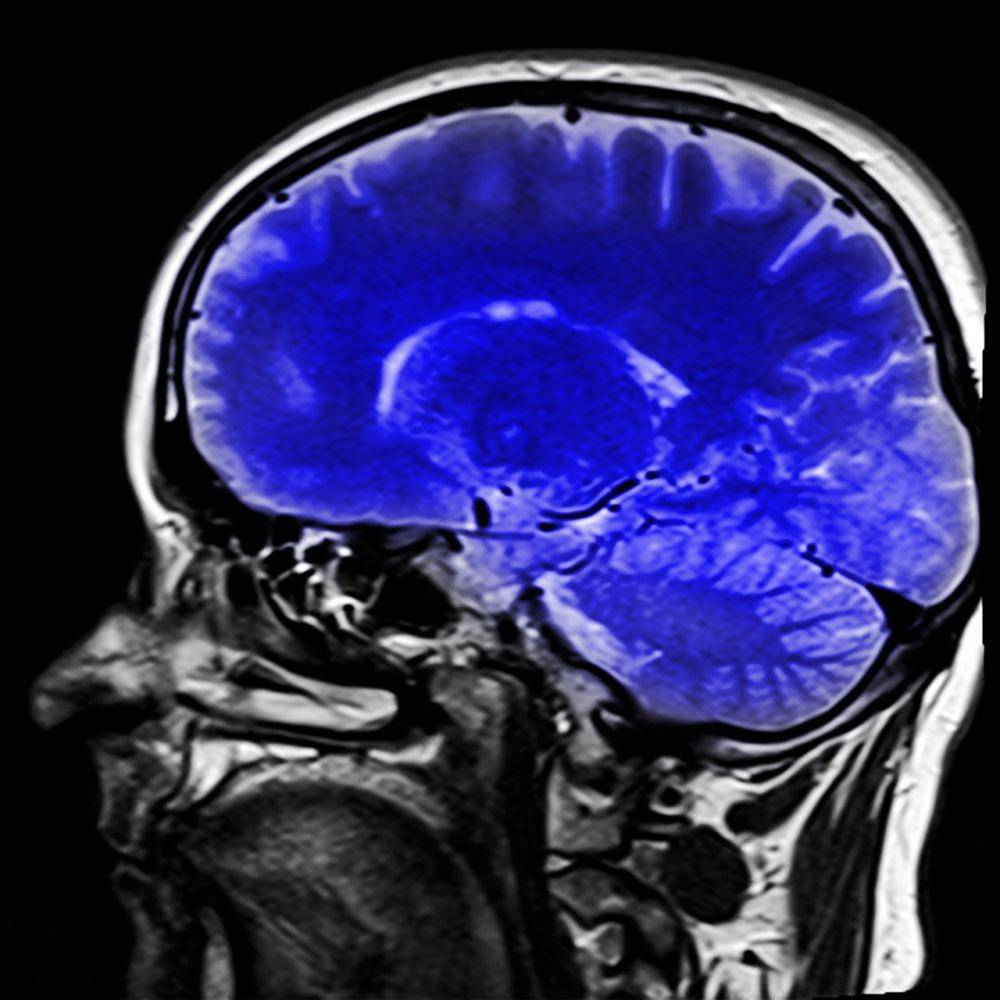

Otak merupakan salah satu organ tubuh terpenting yang paling kompleks dan misterius. Dilansir Live Science organ yang berfungsi sebagai pusat komando dari seluruh aktivitas tubuh ini memiliki berat sekitar dua persen dari berat badan kita.

Salah satu anggapan yang paling populer mengenai otak adalah bahwa manusia hanya menggunakan 10 persen dari kemampuan otaknya. Namun, hal ini hanyalah mitos belaka. Dilansir Winchester Hospital, hasil pencitraan otak (brain imaging) menunjukkan bahwa sebagian besar bagian otak manusia aktif berfungsi, baik saat seseorang terjaga maupun tertidur.